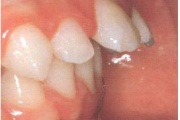

Esimese jäävmolaari ektoopiline lõikumine